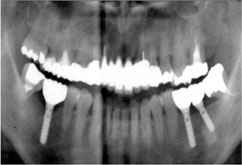

Bさんは数年前に左下の奥歯2本を抜きました。その時の先生は、インプラント治療をやっていなかったので、入れ歯を作りました。Bさんは入れ歯を入れてみて、その違和感にびっくりしました。結局Bさんは、ほとんど入れ歯を使うことなく、はずしたままで過ごしました。なぜなら、入れ歯がなくても反対側の歯で普通に食べることができたのです。Bさんは右側だけで、食べることにしました。

Bさんは数年前に左下の奥歯2本を抜きました。その時の先生は、インプラント治療をやっていなかったので、入れ歯を作りました。Bさんは入れ歯を入れてみて、その違和感にびっくりしました。結局Bさんは、ほとんど入れ歯を使うことなく、はずしたままで過ごしました。なぜなら、入れ歯がなくても反対側の歯で普通に食べることができたのです。Bさんは右側だけで、食べることにしました。

Bさんの右側だけでの食事が数年続いた時、異変がおこりました。右側だけの食事のせいで右の奥歯が悲鳴をあげたのです。Bさんは右の奥歯は1本失うことになりました。

Bさんの右側だけでの食事が数年続いた時、異変がおこりました。右側だけの食事のせいで右の奥歯が悲鳴をあげたのです。Bさんは右の奥歯は1本失うことになりました。

「このままでは、ずるずる歯が無くなっていく。」

Bさんはインプラント治療を選択することにし、私のところにきました。

右に1本、左に2本のインプラントを入れ、Bさんは破壊の連鎖から抜け出すことができました。

多分あのままではもっと破壊が進んでいたでしょう。

破壊の連鎖を食い止めたのは、Bさんの決心なのです。